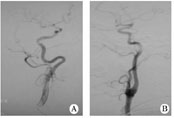

1.1對象2011-08至2012-02在我院住院的缺血性腦卒中患者,經(jīng)腦血管造影篩選出年滿18周歲、頸內(nèi)動脈迂曲(頸內(nèi)動脈彎曲如螺旋狀或有2個或2個以上的彎曲)、而無狹窄或閉塞的患者30例(迂曲組,圖1A),無頸內(nèi)動脈迂曲、狹窄或閉塞的患者30例(無迂曲組,圖1B)。所有患者在腦血管造影前均簽署手術(shù)知情同意書。

圖1患者頸內(nèi)動脈血管造影

A迂曲;B無迂曲